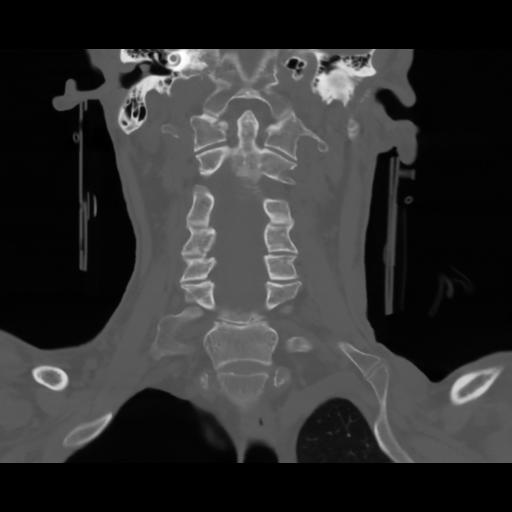

13 P.BLANDAS,,Coronal,2.000,P.BLANDAS,Coronal,